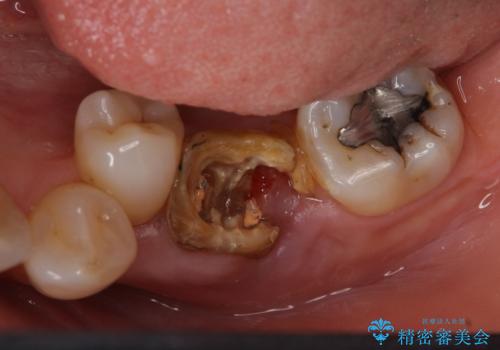

- 左下奥歯の歯ぐきの違和感で来院。

昔神経の治療をした歯が割れてしまっていました。

やむなく抜歯になりましたが、その部分にインプラントを始め希望されましたが、炎症により、骨がなく、かつ歯並びの関係で入れても歯ブラシができずにインプラントも長くもたなそうという診断になりました。